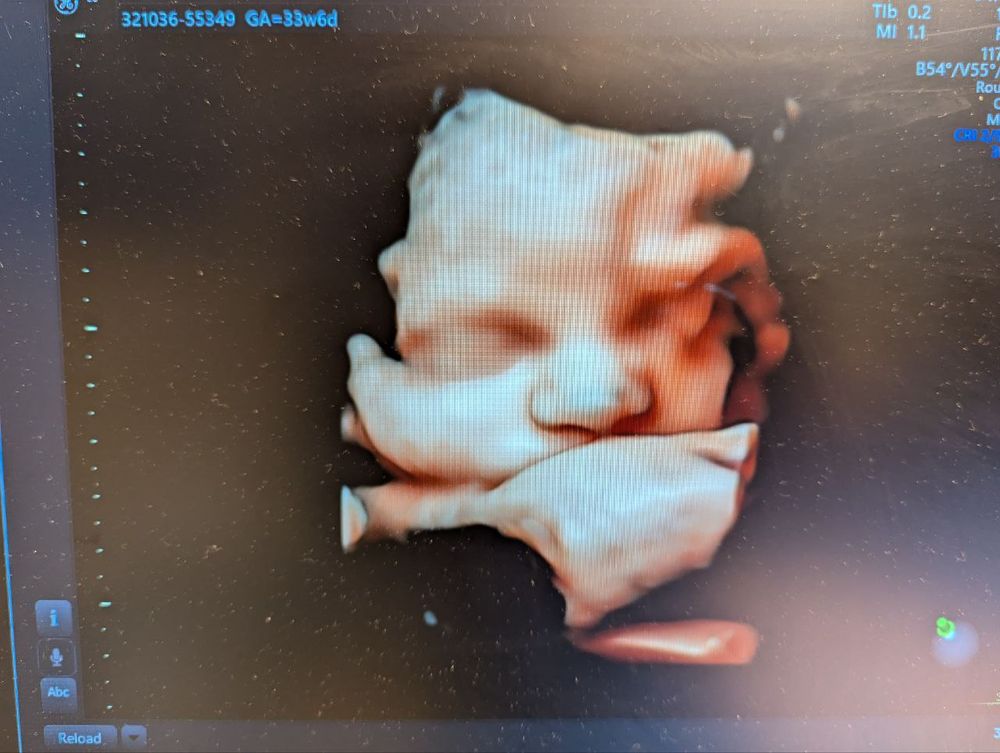

Тревоги на 34 неделе

Екатерина, спасибо большое❤️ Маловесным его не считают: вес 2210, голова больше срока (мы с мужем оба головастики), объем живота по сроку. И ноги до недавнего времени были по сроку. Но на поздних стадиях уже, видимо, всплывает генетика, вариативность, вот это все